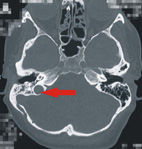

(圖) 箭頭所指為內頸靜脈球位置異常